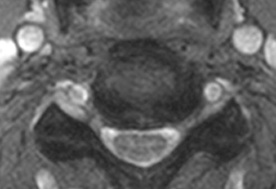

同上 横断画像

左側に突出した椎間板により、頚髄が圧迫されていることがわかります。

左前腕中指から拇指にかけての痛みや痺れ・感覚麻痺等が生じていれば、それらの症状は、この病変を原因としているとみることが可能です。